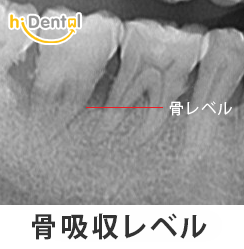

歯科用レントゲン写真は、歯を支える骨の量を評価し、臨床検査では見えない問題を発見するのに役立ちます。